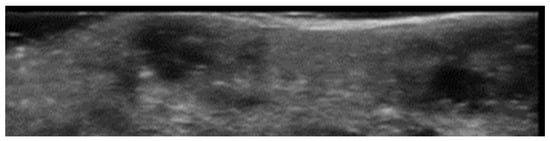

- Mlosek, R.K.; Malinowska, S.P. High-Frequency Ultrasound in the Assessment of Cellulite-Correlation between Ultrasound-Derived Measurements, Clinical Assessment, and Nürnberger-Müller Scale Scores. Diagnostics 2024, 14, 1878. [Google Scholar] [CrossRef]

- Whipple, L.A.; Fournier, C.T.; Heiman, A.J.; Awad, A.A.; Roth, M.Z.; Cotofana, S.; Ricci, J.A. The Anatomical Basis of Cellulite Dimple Formation: An Ultrasound-Based Examination. Plast. Reconstr. Surg. 2021, 148, 375e–381e. [Google Scholar] [CrossRef]

- Sandby-Møller, J.; Wulf, H.C. Ultrasonographic subepidermal low-echogenic band, dependence of age and body site. Ski. Res. Technol. 2004, 10, 57–63. [Google Scholar] [CrossRef]